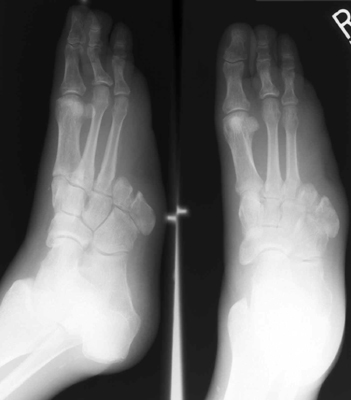

The images to the left show a proximal

transmetatarsal amputation through digits 4 and 5.